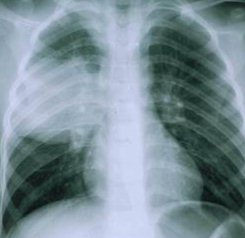

Наличие гельминтов в организме человека подтверждается с помощью визуализирующих лабораторных методов исследования. Как правило, врачи используют для этого рентген, МРТ, КТ и УЗИ. Ранее, наряду с перечисленными методиками, применялась и пункционная биопсия кисты, однако, в наши дни ее считают опасной, поскольку в ходе процедуры может произойти распространение паразитов в окружающие органы и ткани. Также для диагностики эхинококкоза не используются иммунологические методы, что связано с их низкой информативностью.

Легочная форма эхинококкоза приводит к возникновению болей в грудной клетке, кашля, одышки. Если у человека развивается эхинококкоз головного мозга симптомы имеют неврологическую природу. Чаще всего пациенты страдают от параличей, парезов, судорожных припадков и психических расстройств.